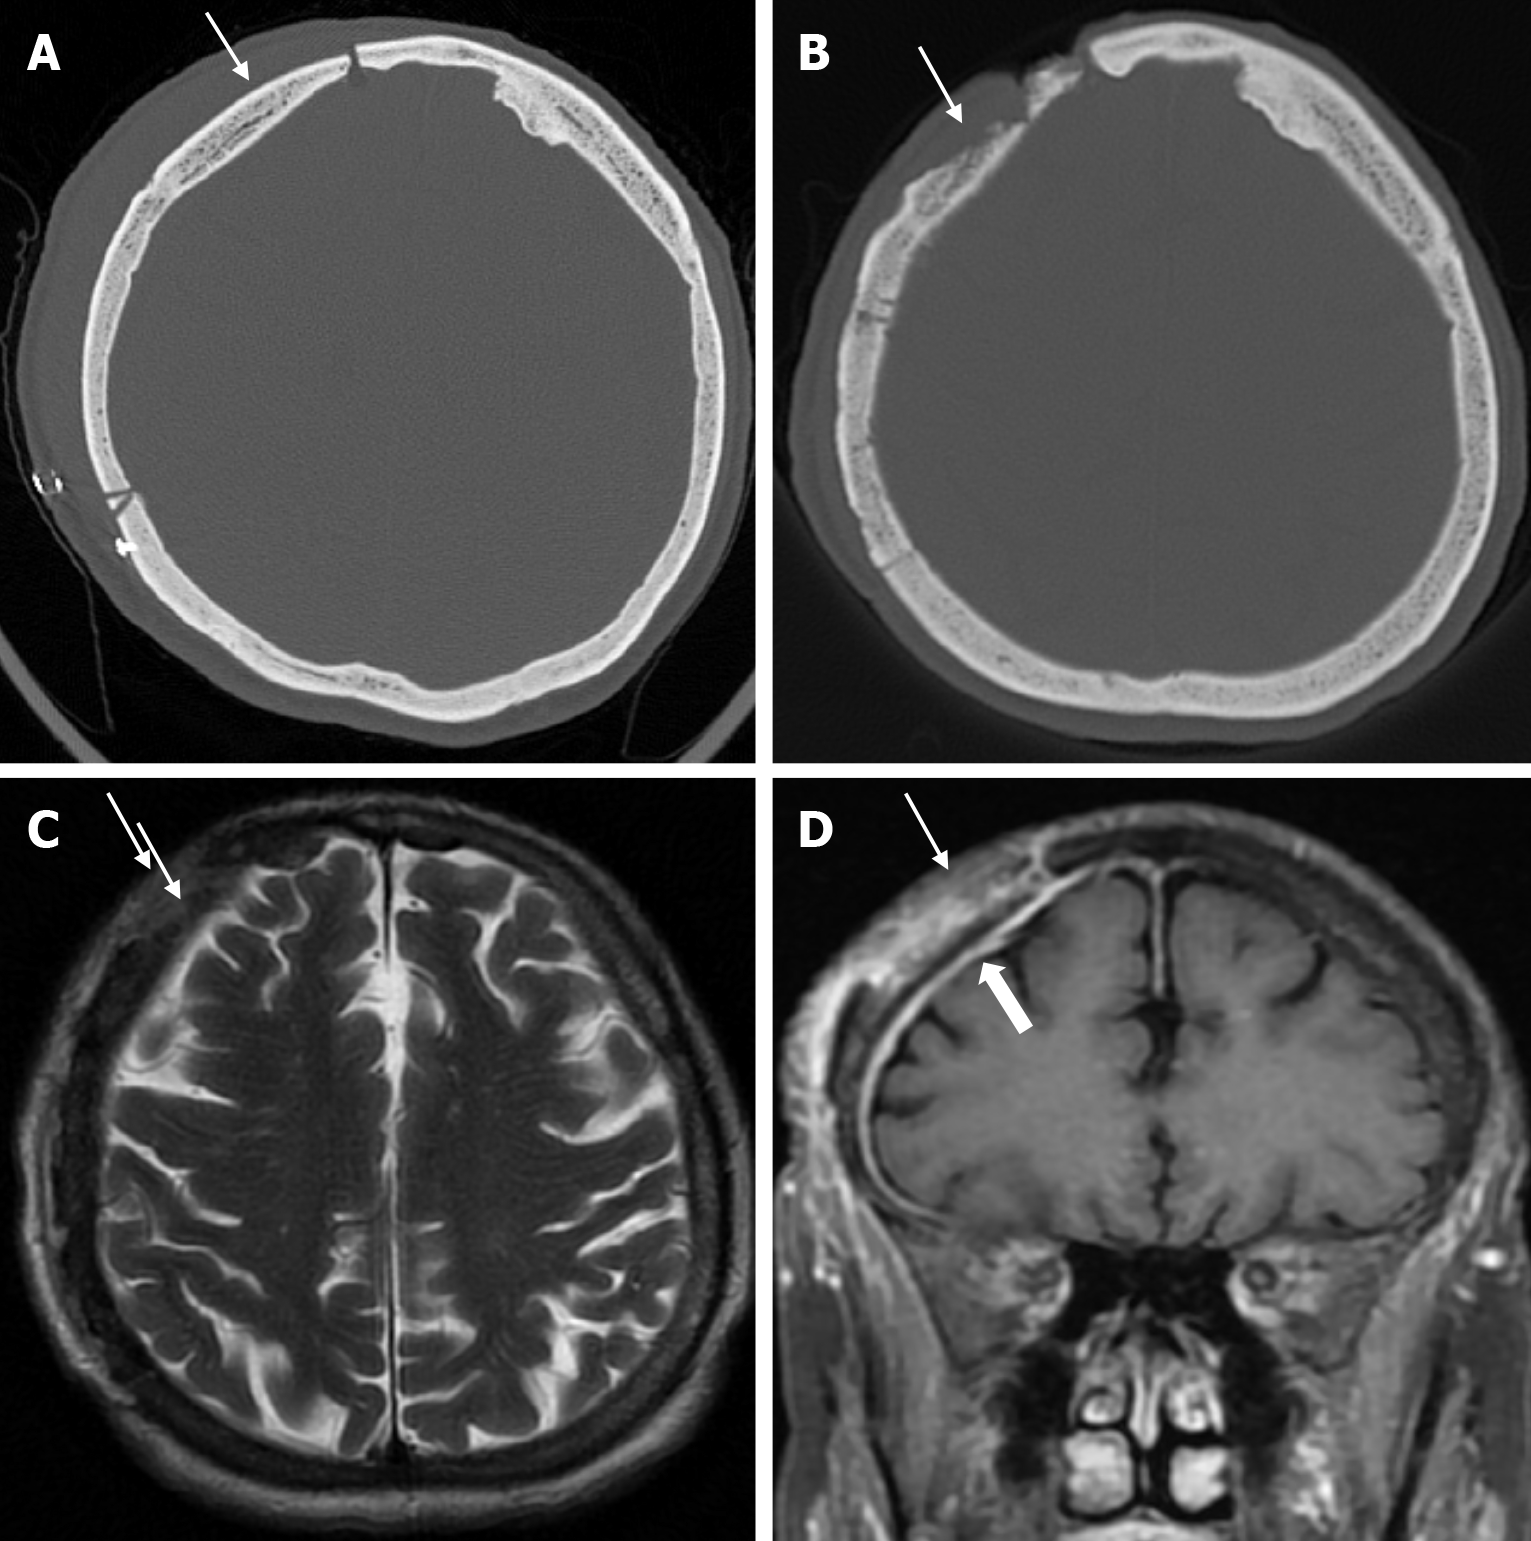

Osteonecrosis of the bone flap after autologous cranioplasty following decompressive craniectomy is a pathology seen in up to 35.1% of cases in adults and is aseptic in most cases. The incidence of bone flap resorption is much higher in the paediatric population, with rates of up to 81.1%. Several potential risk factors have been identified, including large bone flap size, the presence of a shunt system, and a long interval between craniectomy and cranioplasty[32]. In addition, several factors have been implicated in the development of flap osteonecrosis, including young age, multiple fractures, incompatibility between the replanted flap and the adjacent bone, and incorrect cryopreservation storage. Flap osteonecrosis is divided into two distinct categories based on CT characteristics. The more common type 1 flap os